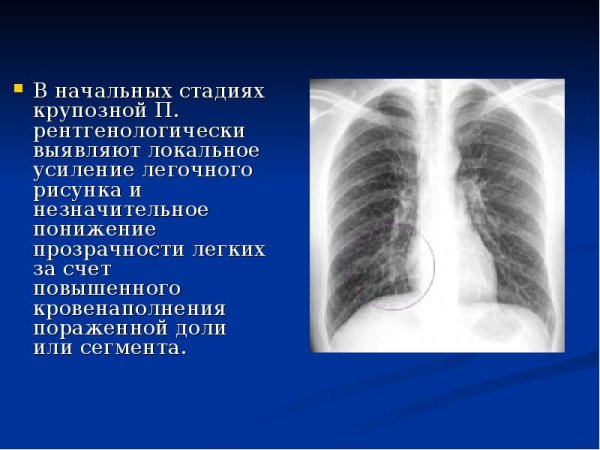

Крупозная пневмония рентгенограмма грудной клетки